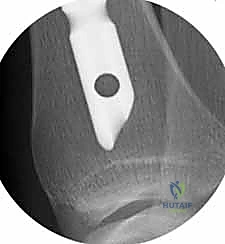

2. وضعية المريض والتدخل الجراحي المحدود (Minimally Invasive)

يُوضع المريض على طاولة عمليات شفافة للأشعة. يقوم البروفيسور هطيف بعمل شق جراحي صغير جداً (حوالي 3-5 سم) في الجزء العلوي من الساق، أسفل صابونة الركبة بقليل (Infrapatellar approach) أو أحياناً فوقها بحسب الحالة.

هذا التدخل المحدود يندرج تحت مفهوم "الجراحة طفيفة التوغل"، وهو ما يقلل الألم بعد العملية ويسرع التئام الجرح.